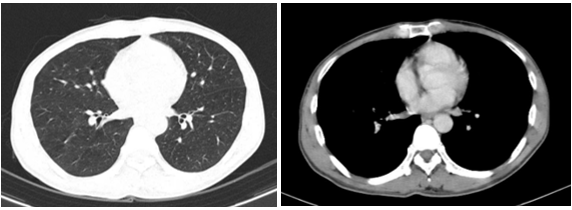

- Chụp cắt lớp vi tính ổ bụng:

Hình 1: Trên hình ảnh CT ổ bụng cho thấy nhu mô gan trái có khối lớn, kích thước khoảng 92x70mm, tỉ trọng hỗn hợp trước tiêm, sau tiêm ngấm thuốc không đồng nhất, có phần ngấm thuốc mạnh thì động mạch, thải thuốc thì tĩnh mạch và thì muộn, tăng sinh mạch trong khối. Khối đẩy lồi bao gan, không thấy thâm nhiễm xung quanh hay hay to lân cận, theo dõi HCC

(ung thư biểu mô tế bào gan) (mũi tên đỏ)

- Chụp cắt lớp vi tính lồng ngực:

Hình 2: Hình ảnh chụp cắt lớp vi tính lồng ngực chưa phát hiện tổn thương nghi ngờ thứ phát